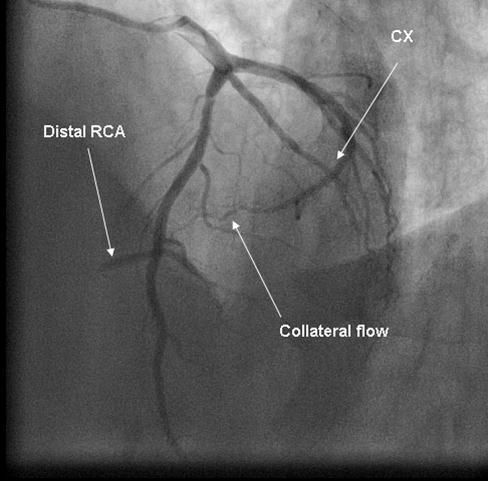

Coronary angiography was again performed. On injections into the left system, collaterals to the distal RCA were demonstrated (figure 1), arising from the left circumflex coronary artery (CX). Injections into the RCA demonstrated tight in-stent restenosis, (figure 2) and a drug eluting stent was successfully implanted. After the angioplasty, injections into the RCA were seen to retrogradely fill the CX (figure 3). The suspicion arose that maybe the left coronary artery had been inadvertently damaged during angiography, so the left coronary was again cannulated and injections performed, demonstrating entirely normal left main and CX arteries. However, the collateral flow that had previously been demonstrated from the CX to the RCA was no longer apparent. On review of the previous angiogram, it was noted that the RCA retrogradely filled the CX despite the original significant stenosis (figure 4). In essence, it became apparent that the bidirectional filling of the RCA from the CX and vice versa was in fact a direct continuity between the vessels and not collaterals, as free flow was noted from the RCA to the CX even when both arteries were completely patent.

Figure 1.Collateral flow from circumflex artery (CX) to right coronary artery (RCA) in cranial left anterior oblique view.